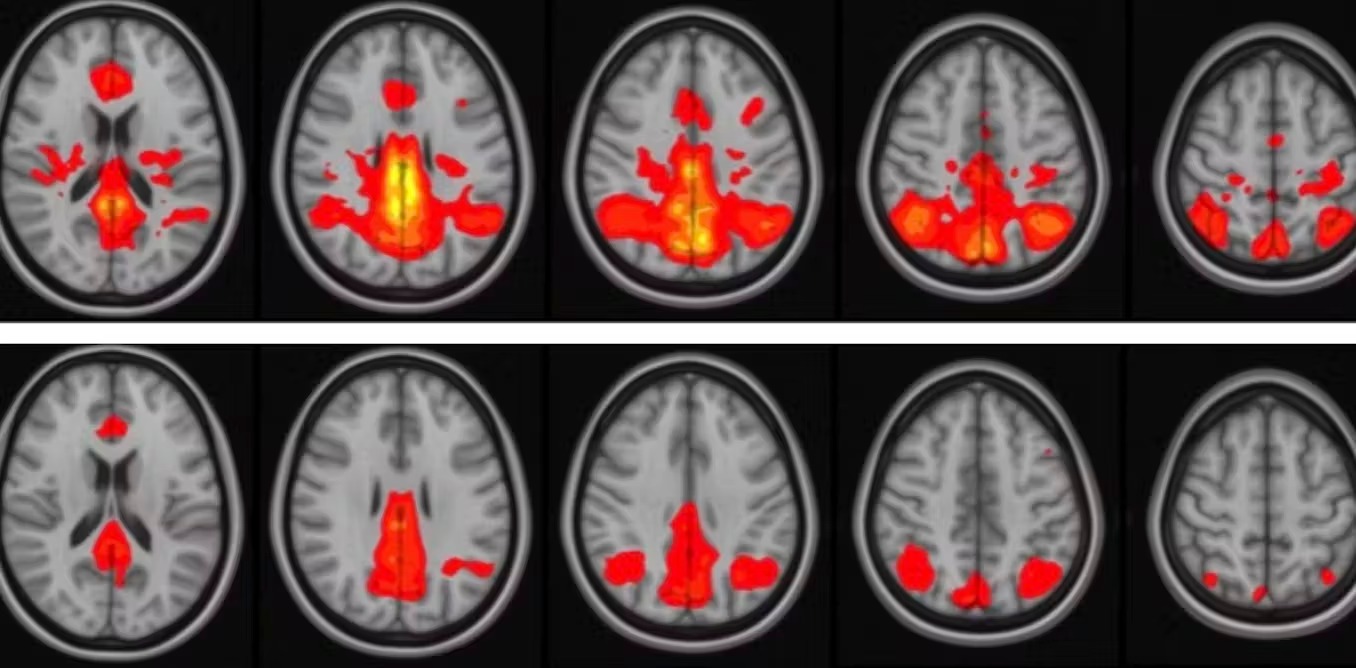

Both these studies used more sophisticated MRI approaches, including resting-state functional MRI which reveals how brain areas communicate with each other, and diffusion tensor imaging that measures the physical integrity of the connections between brain areas.

Many of these factors can be measured in research settings using positron emission tomography scans, or various advanced forms of MRI. Some of these may have predictive power for resilience in the future. Genetic predisposition may be important. People carrying the APOE4 gene or the alpha-synuclein Rep 1 promotor allele may be more at risk for Alzheimer’s or Parkinson’s, respectively, after repeated hits. Other studies have not found such a link.

It is clear that some brains are able to compensate at various levels. This process is likely linked to what is called cognitive reserve, which is the ability of a brain to maintain cognitive function in the face of advancing disease or injury. It has been linked to genetics, level of education, social interactions and health status. It likely depends on the brain’s ability to reroute information, much like a traffic detour — something we can measure with functional MRI. Patients with higher cognitive reserves have better postconcussive outcomes, at least in the short term.